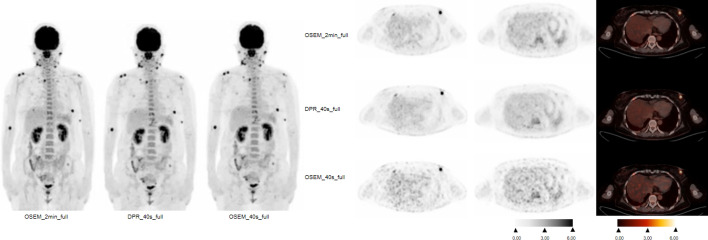

Methods: A total of 87 lymphoma patients (age, 45.1 ± 14.9 years) who underwent 18F-FDG PET imaging for during or post-treatment follow-up from November 2020 to February 2024 were prospectively enrolled. The patients were randomly assigned to two groups, including the 1/3 standard dose group and the standard dose group. Forty-four patients were injected with 1/3 standard dose (1.23 MBq/kg) and scanned for 6 min per bed and were reconstructed: ordered-subsets expectation maximization (OSEM) with 6 min per bed (OSEM_6 min_1/3), OSEM_2 min_1/3 and DPR_2 min_1/3. Forty-three patients were scanned according to the standard protocol (3.7 MBq/kg) and were reconstructed: OSEM with 2 min per bed (OSEM_2 min_full), OSEM_40 s_full and DPR_40 s_full. Additionally, the conventional 5-point scale measurement analysis was performed and DS for lymphoma were determined in different groups. Wilcoxon signed-rank test was used to compare the mean values of liver SUVmax and mediastinal blood pool (MBP) SUVmax in each group. Likert scale and DS were evaluated using Wilcoxon signed rank test.

Results: The patients with OSEM_6 min_1/3 and DPR_2 min_1/3 showed good image quality with 5(5,5) and 5(4,5) of Likert scoring, as well as the patients with OSEM_2 min_full and DPR_40 s_full. No significant difference was found between the OSEM_6 min_1/3 and DPR_2 min_1/3 groups in terms of liver SUVmax and MBP SUVmax (P = 0.452 and 0.430), as well as the patients with OSEM_2 min_full and DPR_40 s_full (P = 0.105 and 0.638). No significant difference was found between the OSEM_6 min_1/3 and DPR_2 min_1/3 groups in terms of lesion SUVmax (P = 0.080). There was a significant differences in lesion SUVmax between OSEM-2 min_full with DPR-40 s_full (P = 0.027). The DS results were consistent (100%) between OSEM-6 min_1/3 with DPR_2 min_1/3, and between OSEM-2 min_full with DPR-40 s_full, respectively.